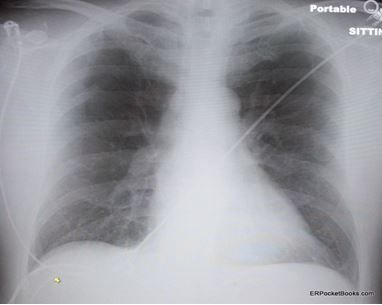

Figure 1. Plain film of chest. (click each figure to enlarge)

Blood work is ordered, including a CBC count, metabolic panel, and cardiac troponin-I, which are all normal. His chest x-ray film (Figure 1) and ECG tracing (Figure 2) are shown at left.

The chest x-ray film is normal, but the ECG shows T-wave inversion in leads V1, V2, and V3-a frequently missed but classic finding in large pulmonary embolisms (PEs). This ECG finding might lead the provider astray looking for an acute coronary syndrome.

The last type of pitfall is related to imaging. It is important to realize that chest x-ray films often are normal or near normal in the presence of PE but may show findings that mimic pneumonia. In addition, patients with PEs may also have CHF or COPD, and these conditions can cause abnormal chest x-ray films. Minimizing exposure to radiation in younger patients is an important consideration. If the chest x-ray film is normal, V/Q scan, when available, is usually the preferred test because it has greater sensitivity, delivers a fraction of the radiation, and does not require IV contrast. If the chest x-ray film is abnormal or if other conditions such as aortic dissection are a consideration, then CT imaging is preferred. Many clinicians favor the CT scan, but it has downsides in addition to radiation exposure and IV contrast: it has lower sensitivity than V/Q scan and a high rate of incidental findings that will require explanation to the patient and often further downstream testing.